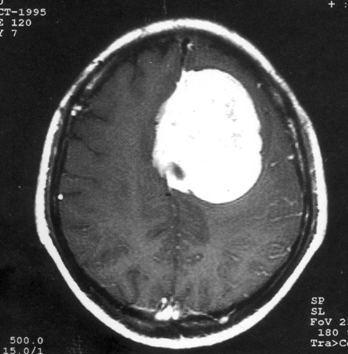

问题 病历摘要:??患者,男,40岁。发作性左下肢抽搐1年余,每次发作3~5分,每周发作1~2次。每次发作后感左下肢乏力,约半日后可自行恢复。既往身体健康。体检:神清,头顶部偏右有局限性骨性隆起(1.5×1.5cm),左鼻唇沟稍浅,伸舌居中。感觉、运动无明显异常。左浅反射减退,左下肢腱反射稍亢进,左Babinski征(-)。 下列对该患者的临床特点分析哪些是正确的?

选项 A.有Jackson癫痫发作 B.有Todd氏麻痹 C.有精神运动性癫痫发作 D.右中央前回可能有刺激性病灶存在 E.右中央后回可能有破坏性病灶存在 F.有失张力发作 G.右锥体束征(+) H.有颅内高压表现

答案 ABDG